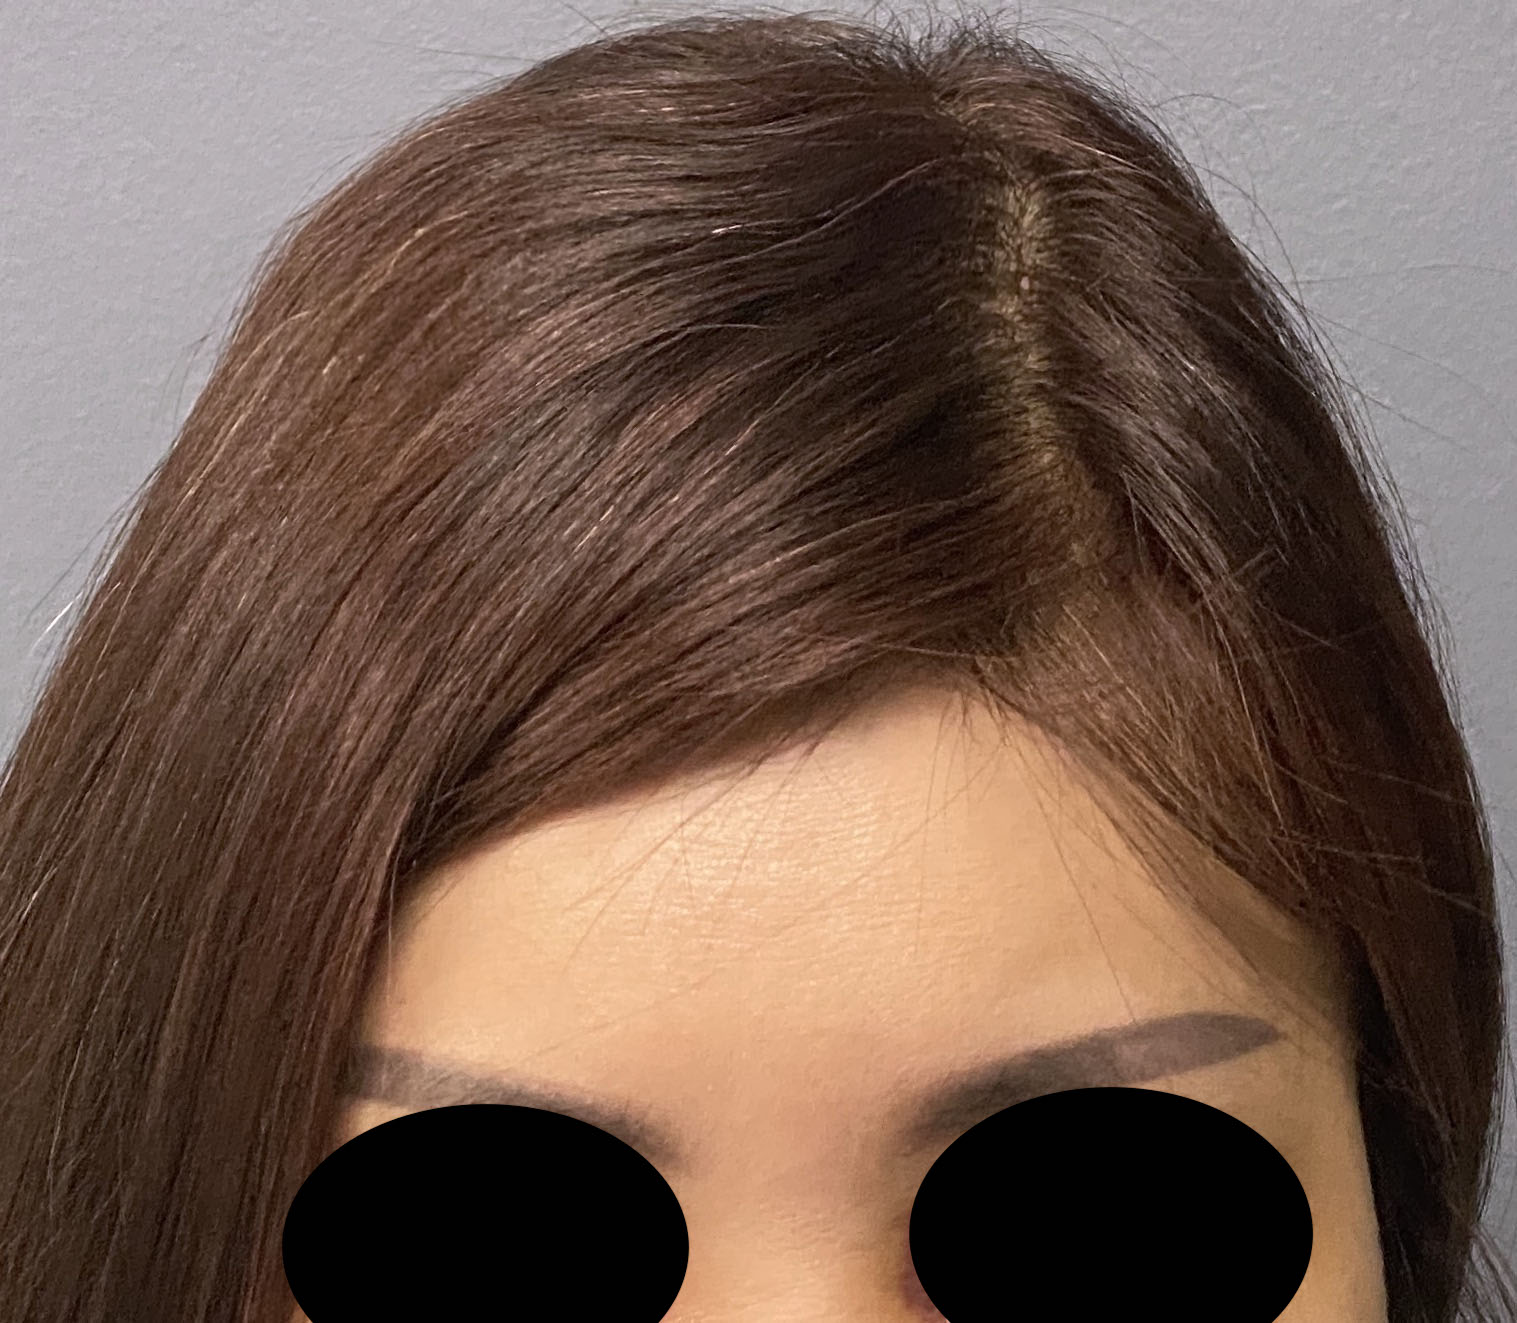

Desire for crown/top of head augmentation which is common for females.

Placement of custom skull implant for crown augmentation.

Desire for crown/top of head augmentation which is common for females.

Placement of custom skull implant for crown augmentation.